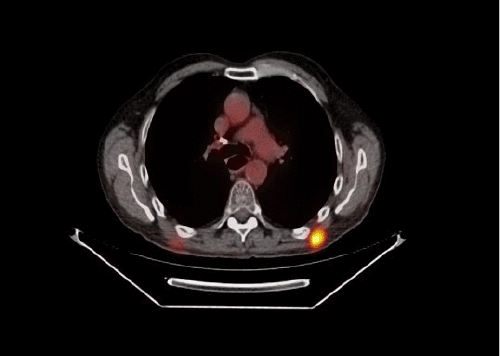

Following a minor procedure, the patient received pathology results. A tumor board discussion at the VAMC determined the need for further staging, leading to a PET/CT scan in which multiple foci of FDG activity were identified in the chest, abdominal wall, and bilateral thighs. To facilitate chemotherapy, a port was placed in September 2019. The patient then underwent palliative FOLFOX chemotherapy, achieving an initial response. Unfortunately, the disease progressed, and the patient passed away in August 2020.

Figure 1. PET/CT Demonstrating FDG-avid Activity in Soft Tissues. Published With Permission

In our case, the skeletal muscle metastases were the first indication that his esophageal adenocarcinoma, which had been treated almost four and a half years earlier, had recurred. His subsequent PET/CT scan demonstrated additional areas of FDG-avidity that were not clinically apparent, underlining the role of these advanced imaging modalities. We elected to remove the symptomatic lesions as a palliative measure.